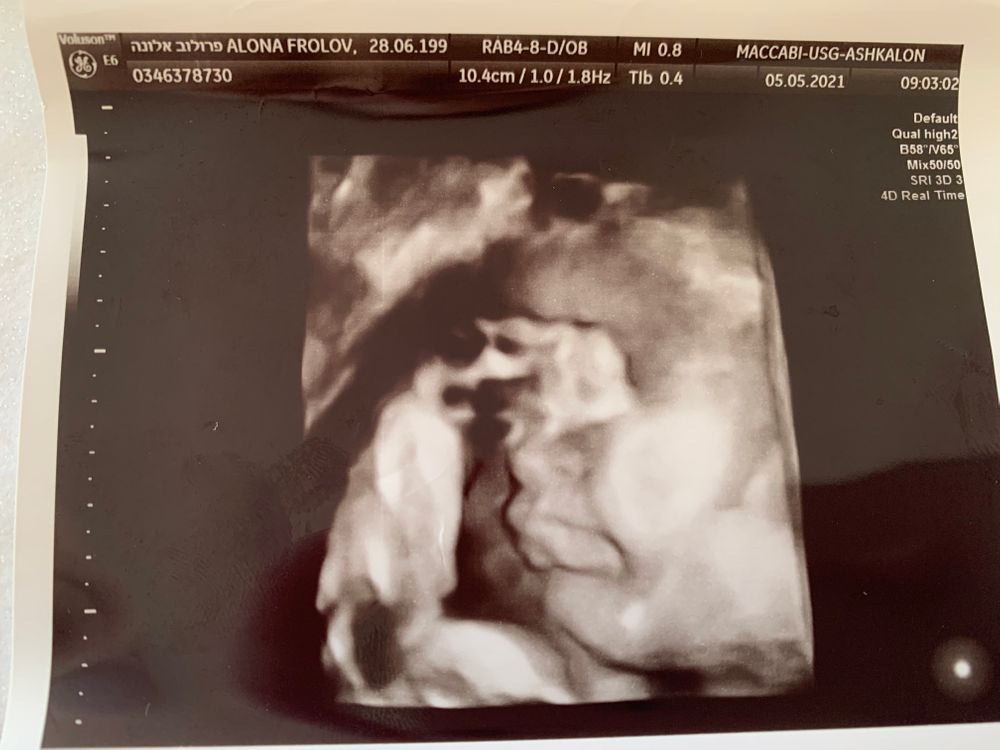

4D снимок, всё ли в порядке? 🧐

УЗИ, КТГ, доплерНесколько недель назад в 34 нед. была на узи, врач решила меня порадовать и показала нашего малыша в 4D и распечатала с собой снимок 😁 Вроде бы всё хорошо, но один момент меня зацепил, до сих пор думаю, может я просто мало видела снимков и не особо что-то понимаю, а может аппарат узи так искажает изображение.. Но не пойму всё ли хорошо с ротиком, губы получились очень странные 🤔А может я накручиваю.

Какой хорошенький малыш/шка 🥰 вы чего? 4д это же не фото, они все такие слегка искаженные, посмотрите в интернете, все у вас в порядке. Тем более как вам ниже написали, если бы что-то было не так врач вам бы сказала

Ущи все-таки не полноценная фотокамера, поэтому изображение может слегка смазываться) на этом фото видно, что малыш как раз был в движении когда фотографировали) не переживайте

Я тоже переживала, наша губки так сложила, будто зайчья губа... Испугалась сильно. Но врач сказала, ты чего, этот момент мы смотрим ещё на первом скрининге. Не переживайте) все хорошо, ребенок в водах, а тут ещё пространство личное нарушили 🤭

Хорошие губки у вас)) если посмотреть на остальные части снимка, там везде все немного искажено, скорее всего помехи) у нас так же было, причём врач под разными углами ставил датчик и делал разный "срез" и эти помехи менялись или проходили)